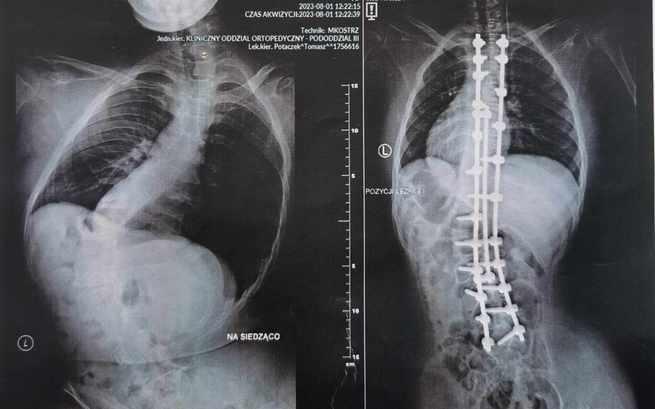

W sierpniu tego roku nasz syn przeszedł poważną operację kręgosłupa, która ratuje mu funkcję siedzenia i oddechu.